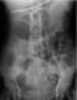

Indwelling nasogastric tube